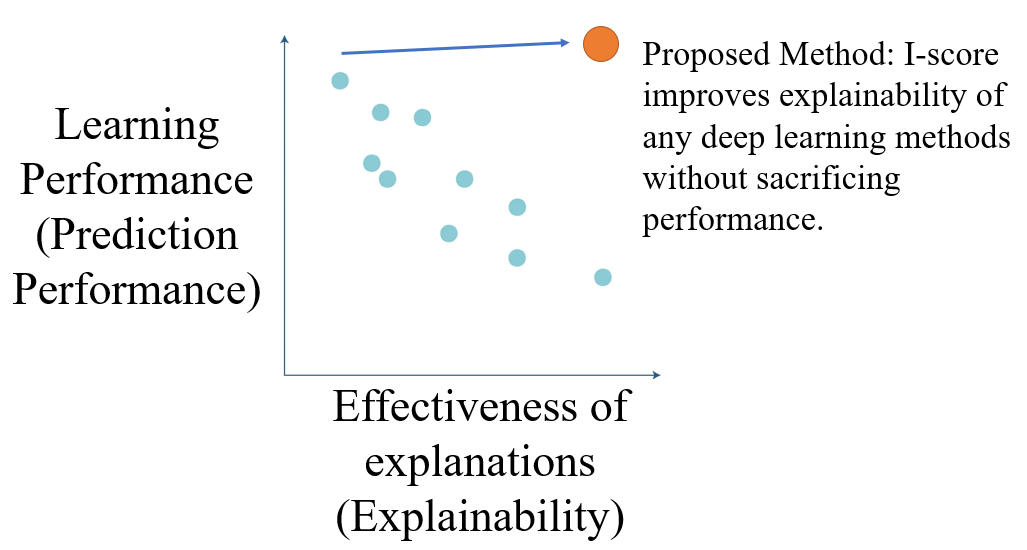

In 2016, DARPA initiated the Explainable Artificial Intelligence (XAI) challenge. The goal is to build suites of machine learning algorithms that are interpretable without sacrificing prediction performance (see Figure 1). The trade-off between learning performance and the effectiveness of explanation is illustrated in Figure 1. The work for this paper delivers a novel interaction-based methodology that produce the power of interpretability and explainability while maintaining state-of-the-art learning performance.

In this paper, we regard the core issue of an XAI problem to be “how features or variables are used to produce the prediction performance”. In other words, the effectiveness of explanations in the DARPA document (see Figure 1) is innately a variable set assessment and selection problem. This means the explainability and interpretability of a machine learning algorithm is directly referring to what measures statisticians use to assess how the features or variables affect the final prediction results. In order to establish accountability, responsibility, and transparency in an AI system, one must first address an explainable and interpretable measure to assess the feature importance. We define the following three dimensions, , , and , for a measure to be interpretable and explainable from statistical and variable assessment perspective. In other words, these three dimensions, denoted by , , and , serve as the key premises of the definition of an explainable and interpretable measure.